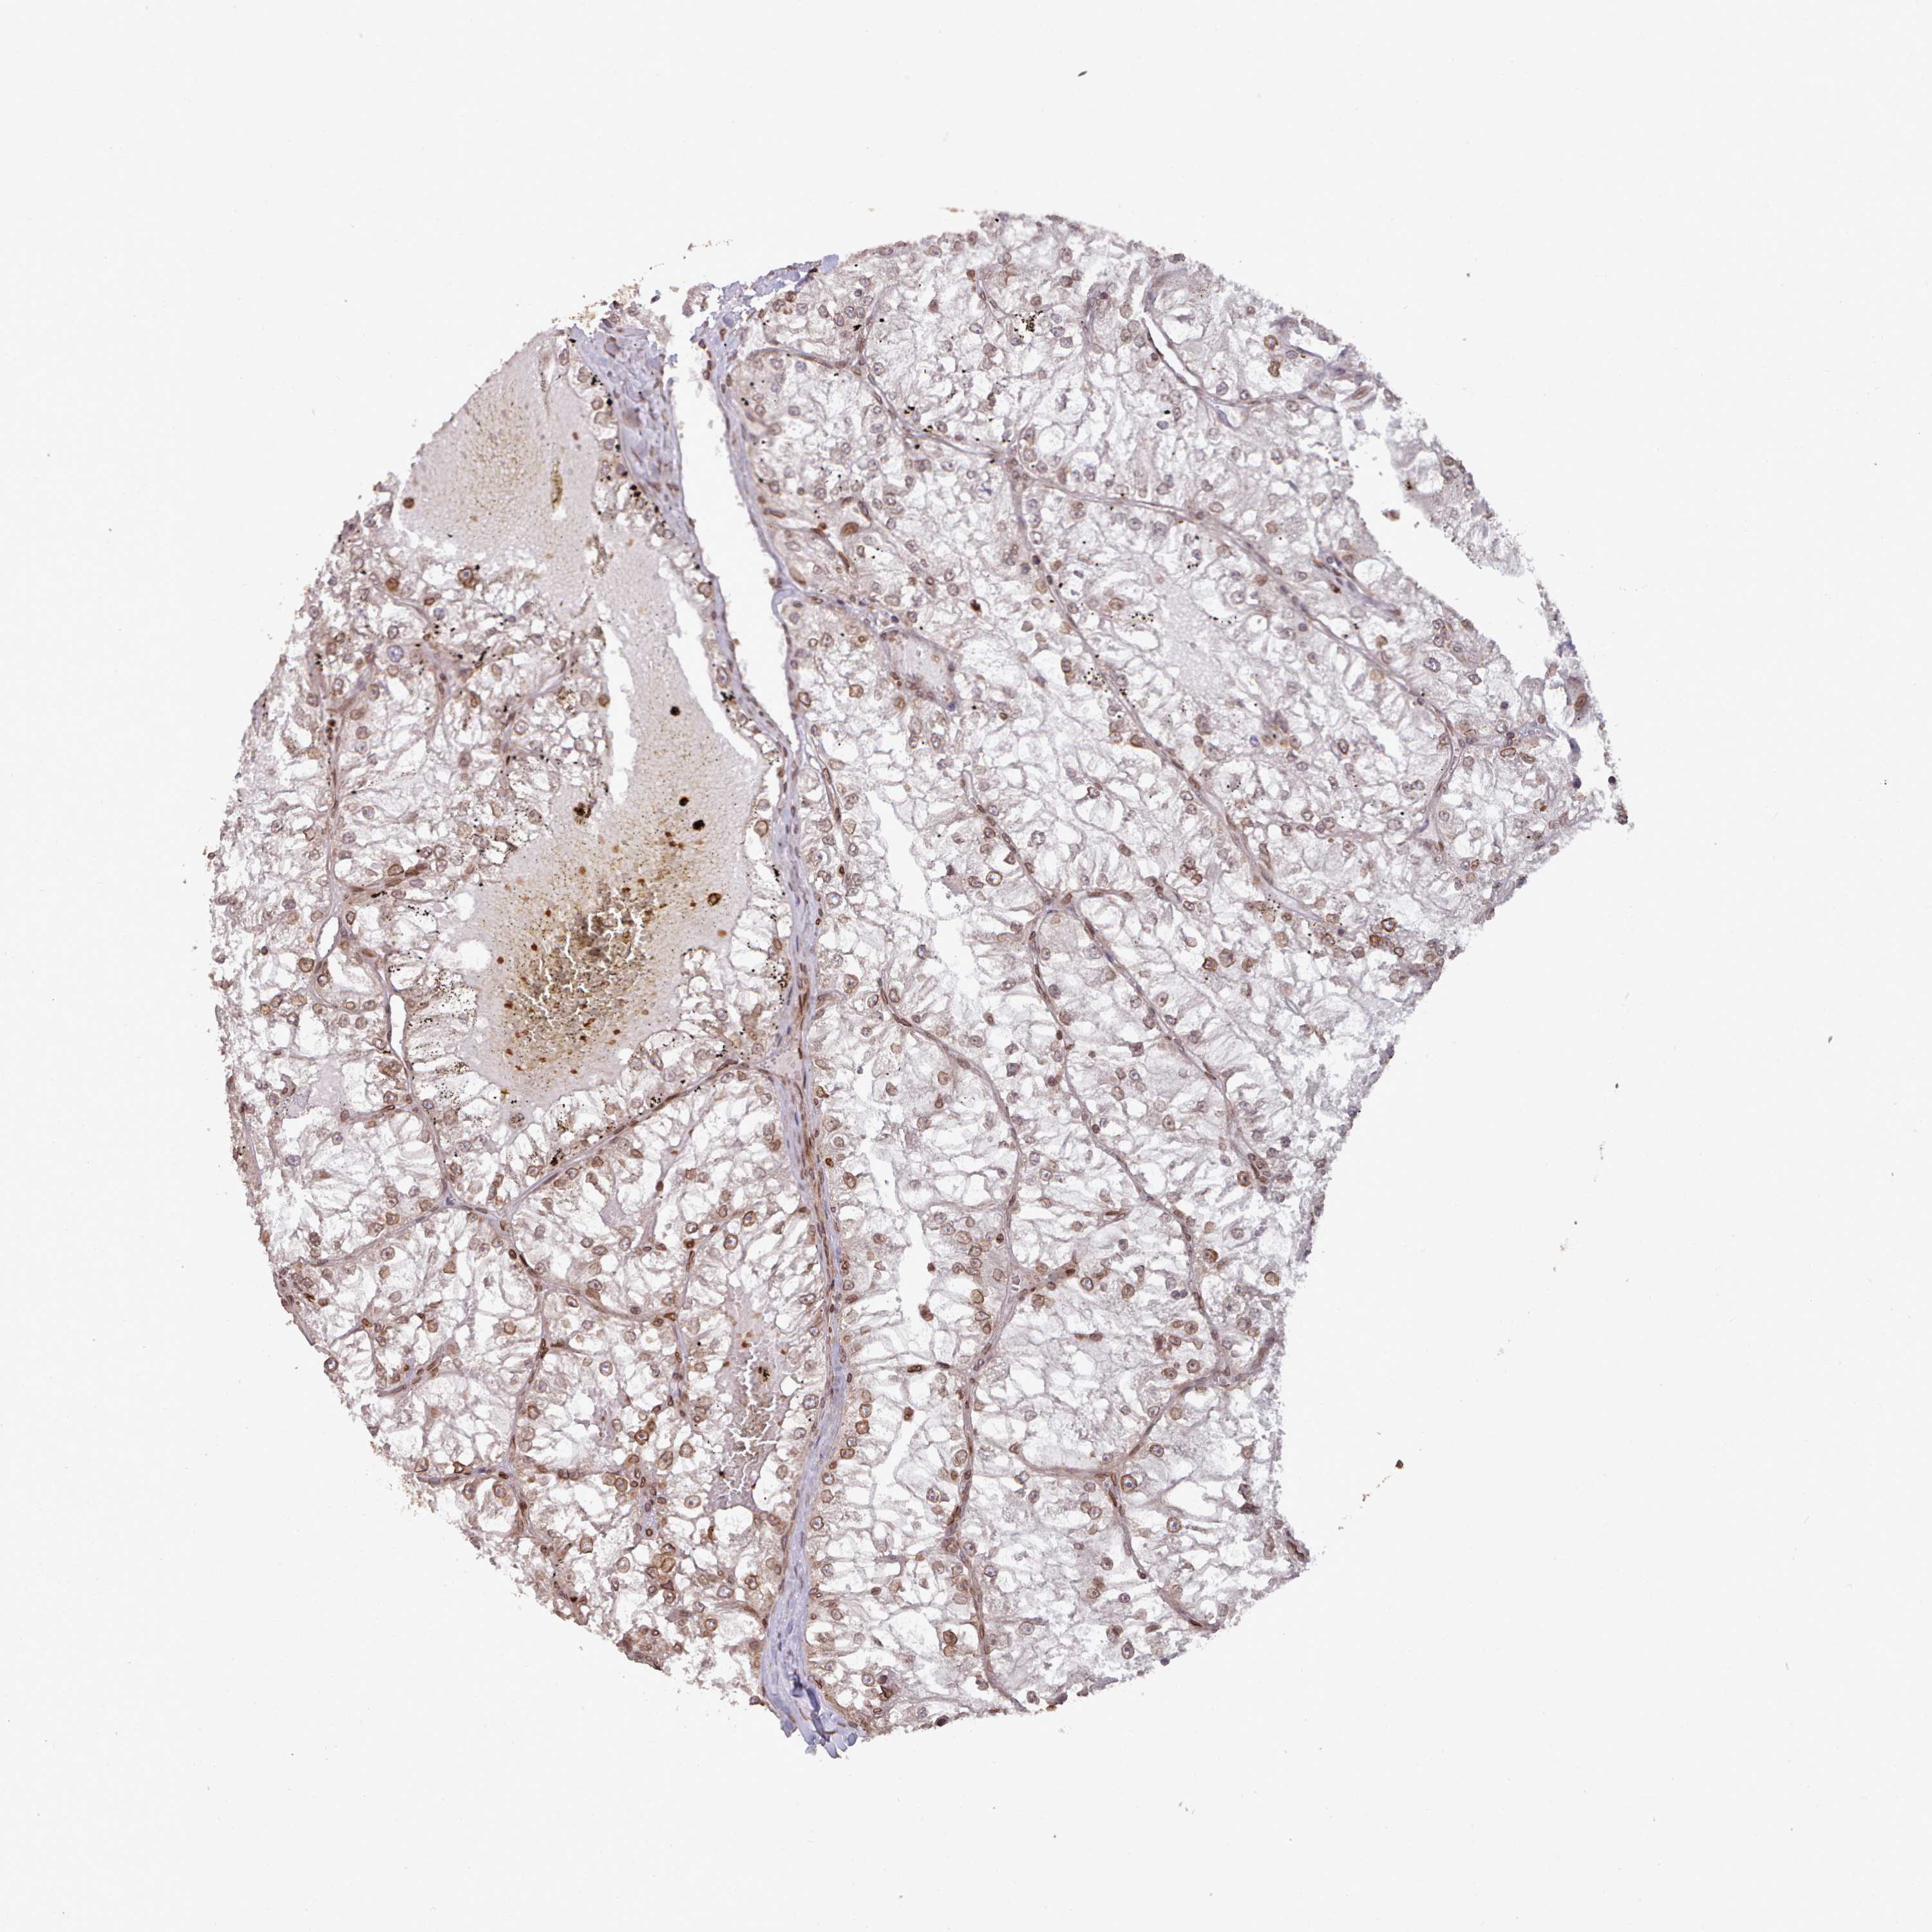

CANCER RENAL CANCER Show tissue menu

KICH TCGA KIRC TCGA KIRC VALIDATION KIRP TCGA PROTEIN RCC CPTAC PROTEIN EXPRESSION

TOR1AIP1 is not prognostic in Kidney Renal Clear Cell Carcinoma (validation)